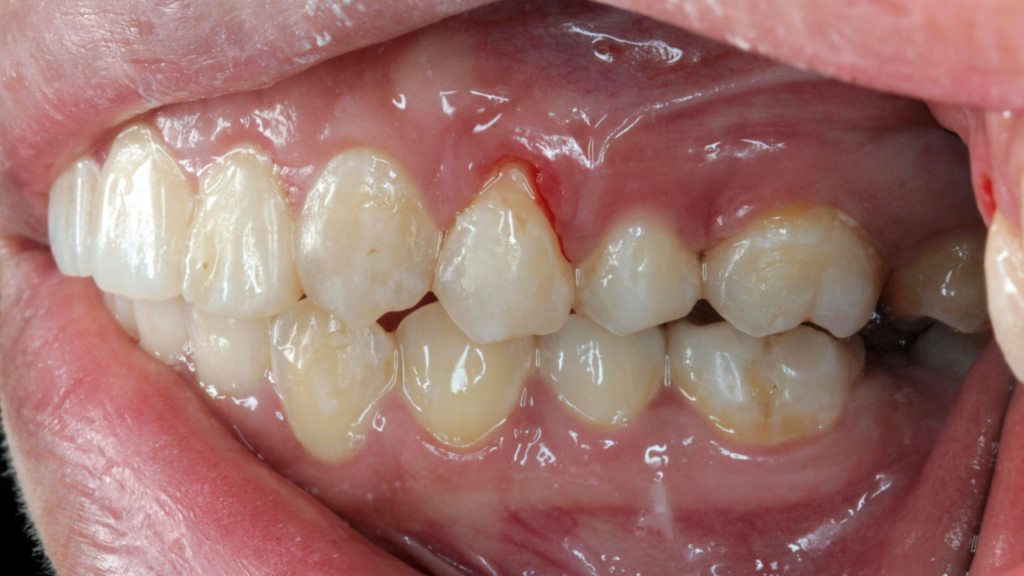

Zapalenie dziąseł i zapalenie przyzębia

Zapalenie dziąseł to początkowy etap choroby przyzębia. Objawia się krwawieniem, obrzękiem i zaczerwienieniem. Nieleczone zapalenie może przejść w zapalenie przyzębia, które prowadzi do uszkodzenia struktur utrzymujących zęby w kości.

Kamień nazębny i płytka bakteryjna

Nagromadzona płytka bakteryjna jest głównym czynnikiem drażniącym dziąsła. Z czasem ulega mineralizacji i przekształca się w kamień nazębny, którego nie da się usunąć domowymi metodami. Obecność kamienia sprzyja przewlekłemu krwawieniu dziąseł.